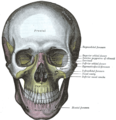

الجمجمة من الأمام.